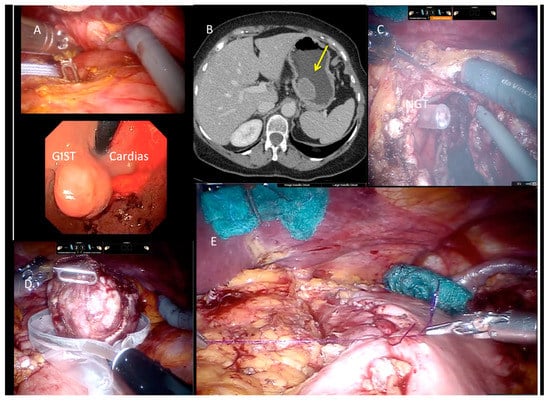

A 5th accessory trocar for the assistant (slightly below the port-line) is placed in the left half of the abdomen. We commonly use a monopolar curved scissors and fenestrated bipolar and prograsp forceps for retraction; sutures are performed using a robotic articulated needle-driver. The intracorporeal anastomosis consists of a manual two layers running suture to close the gastric wall defect. In more detail, we performed a long-term absorbable 2–0 suture or a single barbed suture with a back-and-forth technique (Figure 4, Figure 5, Figure 6 and Figure 7). During robotic operations we do not use energy devices for dissection nor an endoscopic stapler for wedge gastric resections. These devices are reserved for standard gastrectomies. The use of Indocyanine green (ICG) technique during gastric resection to better identify the tumor was performed in 12 cases over 47 (Figure 4 and Figure 6). Post-operative work-up is the same for both techniques.

Figure 4. Use of Indocyanine green (ICG) technique during surgical procedures and GIST resection.

Figure 5. Lesion in CT, endoscopy, and GIST resection.

Figure 6. Endoscopic view of luminal lesion and robotic approach.

Figure 7. Laparoscopic and robotic approach during resection of gastric GIST.

An intraoperative upper endoscopy was performed in 31 cases (38.3%) either to define the exact tumor location in completely endophytic GISTs or to check sutures after gastric wall reconstructions. In five (6.2%) cases an endoscopic intraoperative ultrasound was performed for endophytic lesion identification.